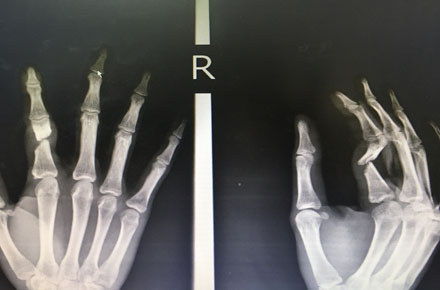

โวยตำรวจขว้างไฟฉายใส่จนนิ้วหัก

ข่าวแรก นายอดิศักดิ์ แซ่อ๋อง นักศึกษาระดับประกาศนียบัตรวิชาชีพชั้นสูง ปี 2 หรือ ปวส.2 วิทยาลัยเทคนิคปัตตานี ออกมาเรียกร้องขอความเป็นธรรม ภายหลังถูกเจ้าหน้าที่ตำรวจในเขตเมืองปัตตานีขว้างไฟฉายใส่จนนิ้วหัก เหตุเกิดระหว่างที่เขาขับขี่รถจักรยานยนต์กับเพื่อนๆ เพื่อเดินทางกลับบ้าน

ข้อมูลจากนายอดิศักดิ์ ระบุว่า เหตุการณ์เกิดขึ้นประมาณเที่ยงคืนของวันศุกร์ที่ 19 ต.ค.61 บริเวณแยกโรงเหล้าสาย ข. ในเขตเทศบาลเมืองปัตตานี ระหว่างที่ขี่รถจักรยานยนต์ตามกันมาห่างๆ กับเพื่อนๆ รวม 3 คัน ปรากฏว่าถูกตำรวจนายหนึ่งขว้างไฟฉายใส่โดยไม่ทราบสาเหตุ เมื่อขับรถต่อมารู้สึกนิ้วชา และมีเลือดไหล จึงจอดรถห้ามเลือด และให้เพื่อนพาส่งโรงพยาบาลปัตตานี

เวลาผ่านไป 3 วัน พ.ต.ท.เรวัติ ศรีจันทร์ทับ รองผู้กำกับการ สภ.เมืองปัตตานี จึงเดินทางมาเยี่ยมนายอดิศักดิ์ที่โรงพยาบาล ซึ่งขณะนั้นนายอดิศักดิ์ได้รับการผ่าตัดนิ้ว และเย็บเส้นเอ็นที่ขาดเรียบร้อยแล้ว แพทย์ใส่เหล็กดามให้ แต่ยังต้องฉีดยาทุกๆ 6 ชั่วโมง และห้ามขยับนิ้ว โดยเขาย้ายไปพักรักษาตัวในห้องพิเศษของโรงพยาบาล ท่ามกลางการดูแลอย่างใกล้ชิดของครอบครัว

บรรยายภาพ :

1 ภาพเอ็กซเรย์นิ้วที่หักของ นายอดิศักดิ์ แซ่อ๋อง